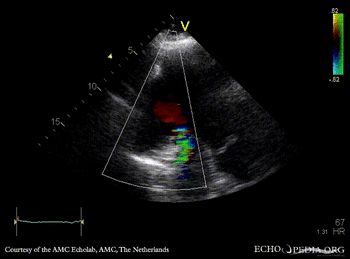

Large pseudoaneurysm of posterior wall

PLAX: large pseudoaneurysm of posterior wall PLAX: Color Doppler, severe mitral regurgitation